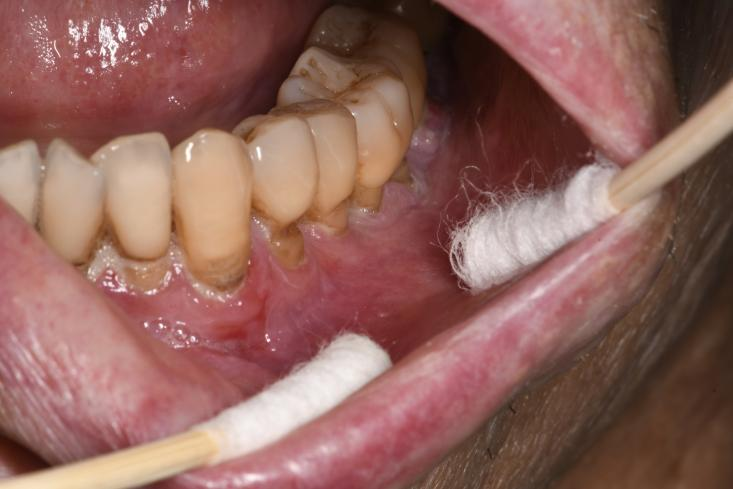

黏膜的炎症、糜烂与溃疡是疼痛的直接来源,约96.2%的口腔cGVHD患者主诉疼痛7,严重干扰咀嚼、吞咽和言语功能。当溃疡累及唇部等血管丰富的区域时,易导致反复出血,进一步加剧患者的身心负担。研究显示,影响患者口腔健康相关生活质量(OHRQoL)的主要因素是口腔疼痛与敏感症状,而非美国国立卫生研究院口腔黏膜评分量表(NIH OMS)8,提示患者的痛苦感受可能远超临床体征的“直观表现”。

cGVHD口腔表现:红斑、苔藓样损害、溃疡及假膜形成(图片源自陶人川教授团队)

cGVHD黏膜出血表现(图片源自陶人川教授团队)